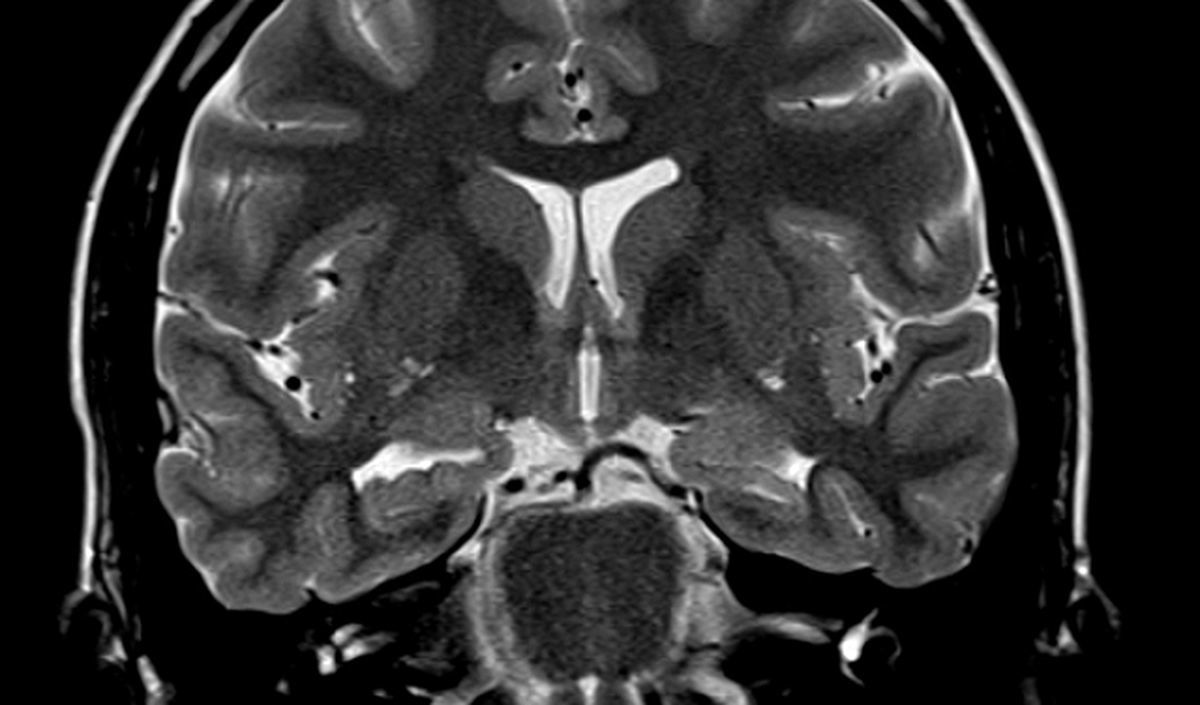

سیستم «DishBrain» با ادغام سلولهای عصبی انسانی مشتق از سلولهای بنیادی با تراشههای سیلیکونی ساخته شده و امکان ایجاد یک پلتفرم هیبریدی را فراهم میکند که ویژگیهای مغز و توان محاسباتی را همزمان دارد. این اولین کامپیوتر زیستی تجاری جهان است که با نام «CL1» عرضه شده است.